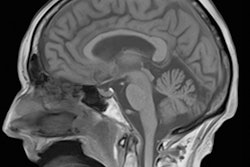

RsfMRI can be used to evaluate regional interactions that occur when a patient is not performing an explicit task. It works by observing changes in brain blood flow, which create a blood oxygen level dependent (BOLD) signal. Resting-state functional connectivity research has revealed a number of networks that are consistently found in healthy subjects and recognized through specific patterns of activity, and now researchers are using the technique to explore altered functional organization in neurological or psychiatric diseases.

Because rsfMRI has the potential to become a key technique in brain imaging, MRI specialists are keen to understand the obstacles to routine use, and if, when, and how this technique could be applied to patient and treatment evaluation. In answer to the question "Is rsfMRI clinically relevant?" which was the title of the hot topic debate, the correct response is "not in isolation," according to Steve Williams, PhD, professor of imaging sciences and head of the neuroimaging department at King's College London (KCL). He warns that looking at brain activity data from rsfMRI was akin to listening only to the double bass section of the orchestra.